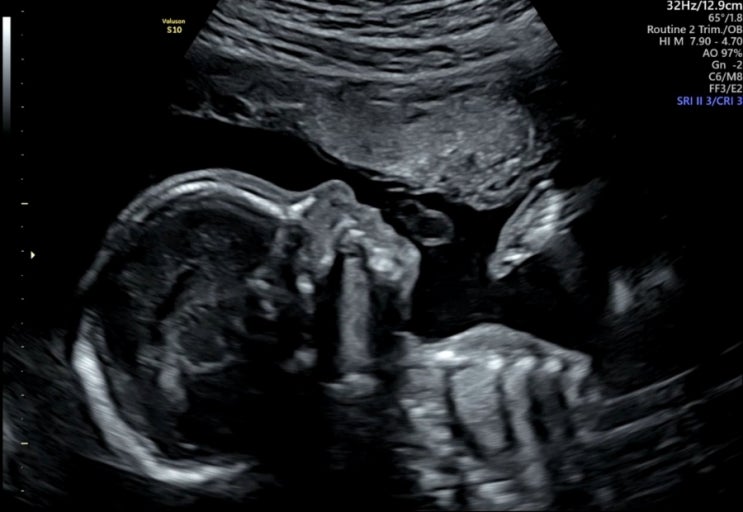

임신21주) 강릉 정밀초음파 후기

삼척, 동해에는 정밀초음파를 따로 안본다고 의료원에서는 강릉 세가온이나 아이앤맘에서 보고 오길 추천해...